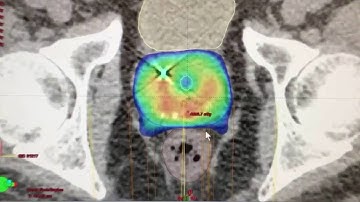

Session 5 - SBRT Simulation and Registration - Motion Management